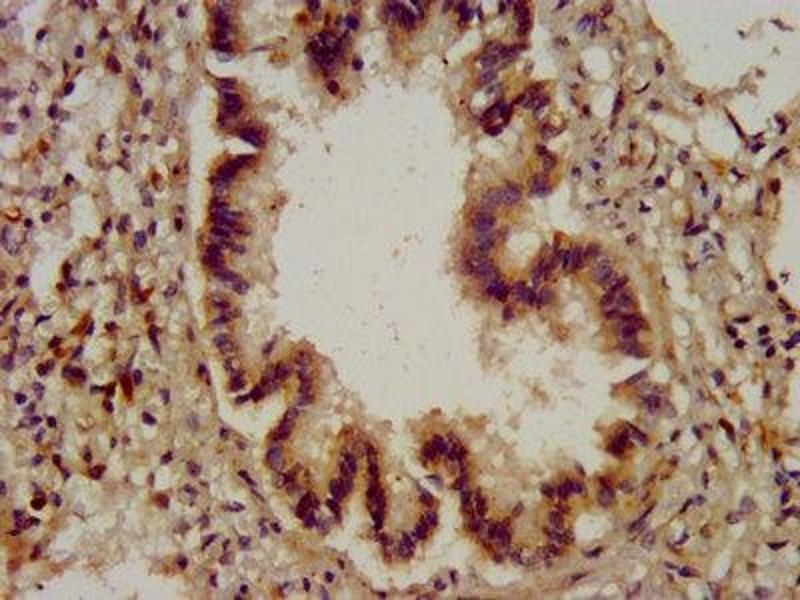

CYBA anticorps (AA 128-195)

- CYBA Antibody

- Recombinant Human Cytochrome b-245 light chain protein (128-195AA)

Aliases: CYBACytochrome b-245 light chain antibody, Cytochrome b(558) alpha chain antibody, Cytochrome b558 subunit alpha antibody, Neutrophil cytochrome b 22 kDa polypeptide antibody, Superoxide-generating NADPH oxidase light chain subunit antibody, p22 phagocyte B-cytochrome antibody, p22-phox antibody, p22phox antibody